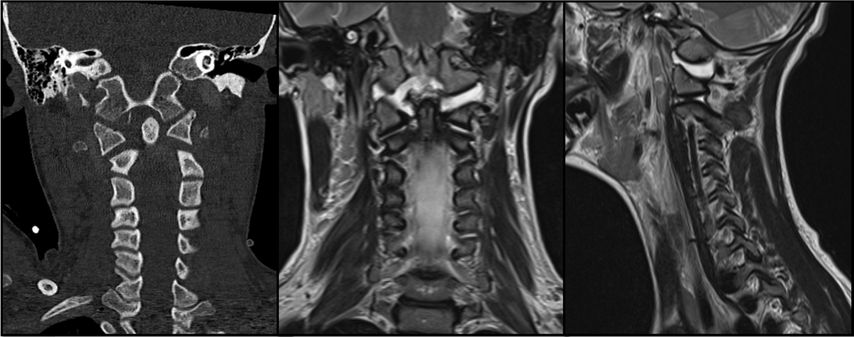

Abb. 1: CT und MRT eines pädiatrischen Patienten mit einer Typ-I-AOD und atlantoaxialer Dislokation nach Verkehrsunfall

AOD stellt die schwerste Verletzungsform im kraniozervikalen Bereich dar und ist für etwa 6–10% aller tödlichen Verletzungen der Halswirbelsäule verantwortlich. Sie tritt in über 30% der tödlichen Fälle nach Verkehrsunfällen auf und zeichnet sich durch eine hohe Letalität aus.5 Der häufigste Verletzungsmechanismus bei der kraniozervikalen Dislokation ist eine Hyperextension infolge stumpfer Gewalteinwirkung. Dabei kommt es häufig zum Riss der Membrana tectoria. Aufgrund des disproportionalen Verhältnisses zwischen Kopf und Körper sind pädiatrische Patient:innen bei Verkehrsunfällen mit hoher Geschwindigkeit besonders gefährdet. Atlantookzipitale Dissoziationen werden traditionell nach der Klassifikation von Traynelis et al.6 in drei Typen eingeteilt: Typ I beschreibt eine anteriore Verschiebung des Okziputs relativ zum Atlas, Typ II eine longitudinale Dislokation und Typ III eine posteriore Verschiebung des Okziputs gegenüber dem Atlas. Die aktuelle Harborview-Klassifikation erlaubt im Vergleich zum oberen Klassifikationssystem eine detailliertere Bewertung der Operationsindikation, da sie auf MRT-Befunden basiert und insbesondere den Grad der Dislokation berücksichtigt. Sie unterscheidet drei Verletzungstypen; TypI stellt eine stabile Verletzung dar, bei der häufig lediglich eine unilaterale Schädigung der kraniozervikalen Bänder vorliegt. In diesen Fällen ist eine konservative Behandlung in der Regel erfolgreich. Ab Typ II wird eine dorsale okzipitozervikale Fusion unter Verwendung von Plattensystemen empfohlen.